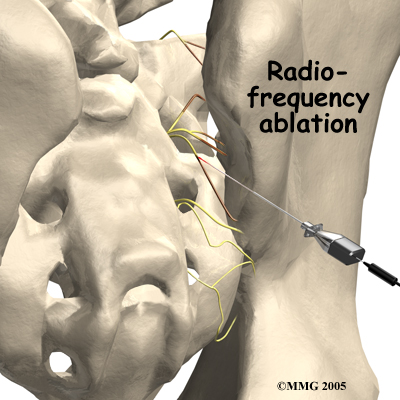

Another procedure that has been somewhat successful for chronic SI joint pain is called radiofrequency ablation. After a diagnostic injection has confirmed that the pain is coming from the SI joint, the small nerves that provide sensation to the joint can be "burned" with a special needle called a radiofrequency probe. In theory, this destroys any sensation coming from the joint, making the joint essentially numb. Unfortunately this procedure is not always successful. If it does help, it is temporary but can last for up to two years and can be repeated if needed.